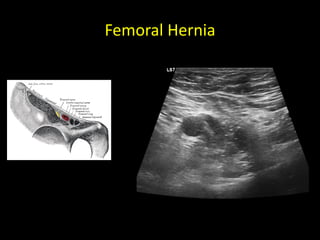

Femoral Hernia